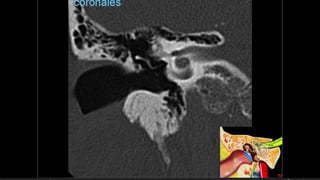

Evaluación Imagenologica

• #38 Izqu. AXIAL-- fxLongitudinal perdonan la capsula otica (laberinto oseo) Centro AXIAL fx trnasversa lascuales tperdonan el lab erinto oseo Dere: MIXTA – tmp perdona